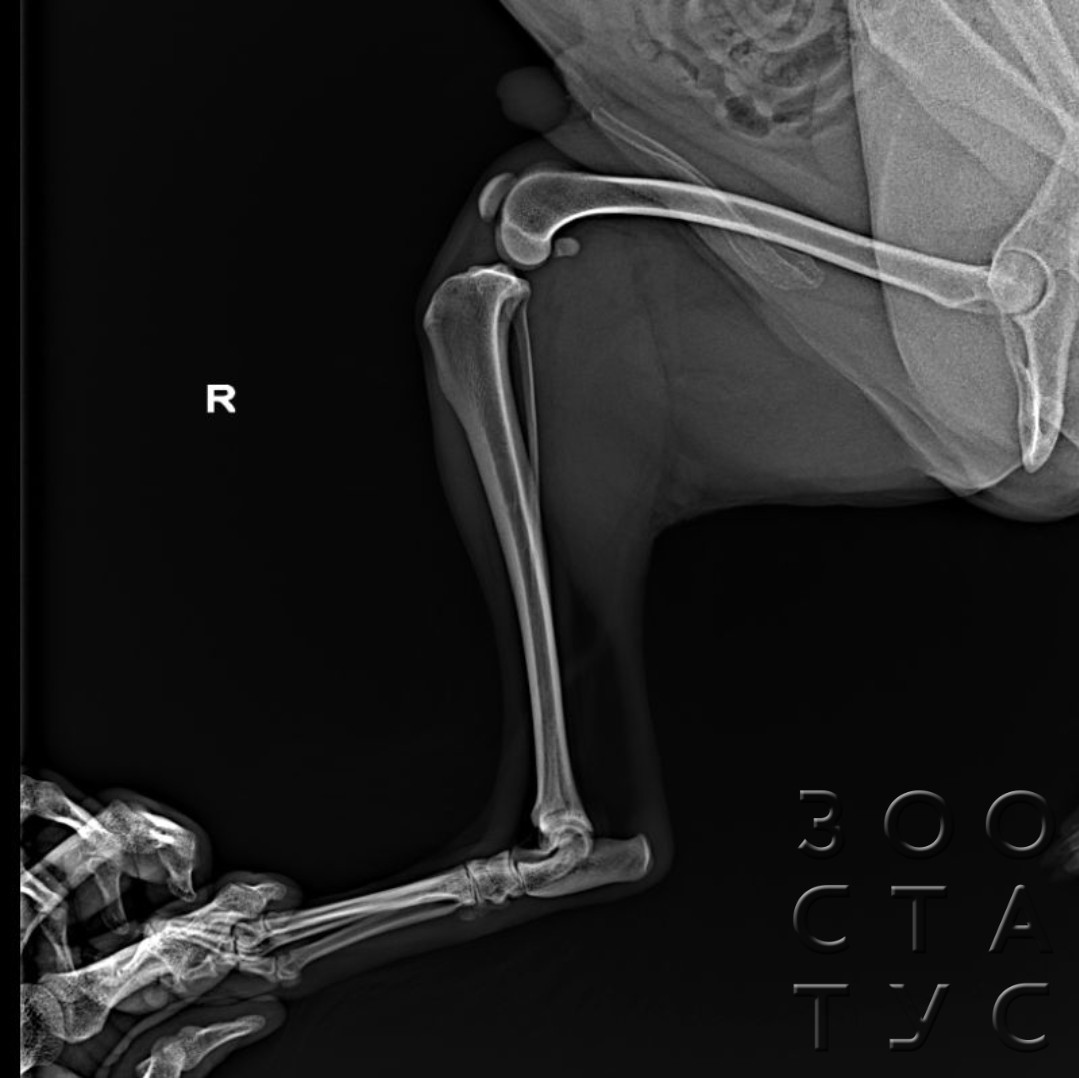

Рентгеновские снимки анатомии собак: строение и здоровье